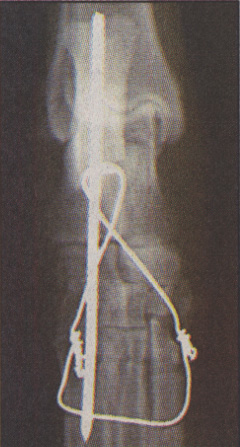

X-ray of the wired leg.

A horse-riding dog returned to the saddle at the weekend after a five hour operation on her broken leg which left her owners with a £500 bill.

Jessie, a collie, was given a bone graft and had the leg wired and pinned after jumping off a vehicle and landing awkwardly three months ago.

She had become a familiar sight riding on the back of the horse Jim as he pulled a tourist barge along the Grand Western canal in Tiverton, Devon.

Jessie's owners, Ray and Pat Brind, of the Grand Western Horseboat Company, said it was feared she would lose her leg after the accident.

"Our thoughts were for Jess and how we could do the best for her. We would have been devastated to lose her," said Mrs Brind. "She has a limp, but that should improve when the wire is removed."

Daily Telegraph, Monday May 26, 1997.